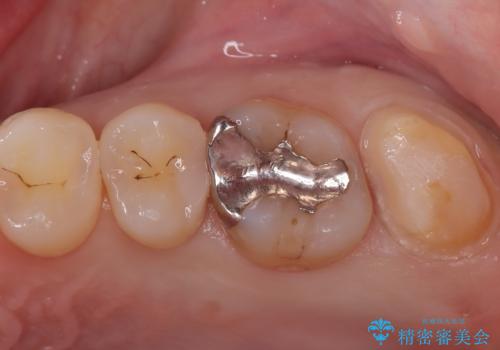

- 「冷たいものが強くしみる」という主訴でご来院されました。精密な診査の結果、虫歯が非常に深く、通常であれば神経を全て抜く「抜髄(ばつずい)」が必要な状態でした。しかし、神経を抜くと歯の寿命が縮まってしまうため、今回は神経の一部を温存する**「部分的断髄法(VPT)」**を提案しました。高い殺菌性と封鎖性、そして組織の再生を促す効果を持つMTAセメントを使用して神経を保護し、最終的には強度と審美性に優れたセラミックで修復する計画を立案しました。

部分的断髄法(MTAの使用): ラバーダム防湿を行い、無菌的な環境下で虫歯を慎重に除去。神経の露出を確認した後、炎症を起こしている一部の神経のみを除去し、残りの健全な神経を保護するためにMTAセメントを充填しました。これにより、神経の機能を維持し、歯を内部から守ることが可能となりました。